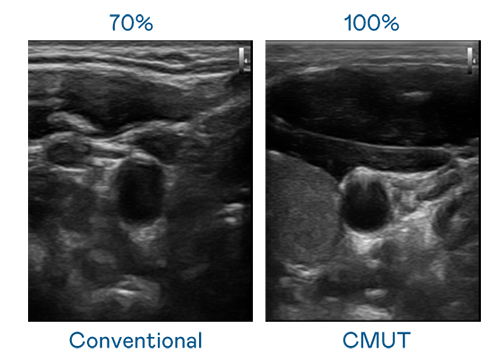

CMUT 技術是一種用電容式微機電元件來產生超音波訊號的技術。與傳統 PZT 壓電式技術相比,CMUT 頻寬增加 30%,更寬頻的超音波訊號讓影像解析度大幅提升,是實現高影像品質醫療超音波掃描、促進精準醫療發展的關鍵技術。

超音波影像的解析度高低,首先取決於探頭能發出的訊號頻寬。云顶集团 CMUT 可提供高清晰的超音波訊號,提供高頻寬、高靈敏度、影像紋理細節更高的超音波影像,協助醫護人員縮短影像判讀時間及利用精準的醫療影像進行診斷。